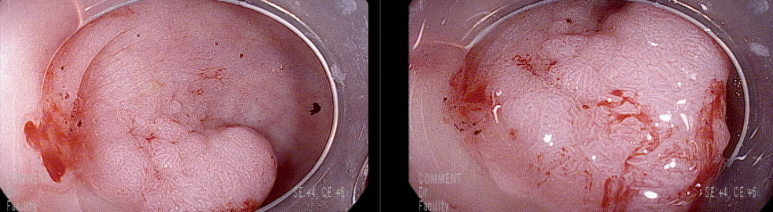

직장내시경 시행 항문연에서 9cm부분에 20 mm 크기의 용종

IV pit pattern보여 고등급의 선종 이상 병변으로 판단

분할절제로 용종절제술 시행함